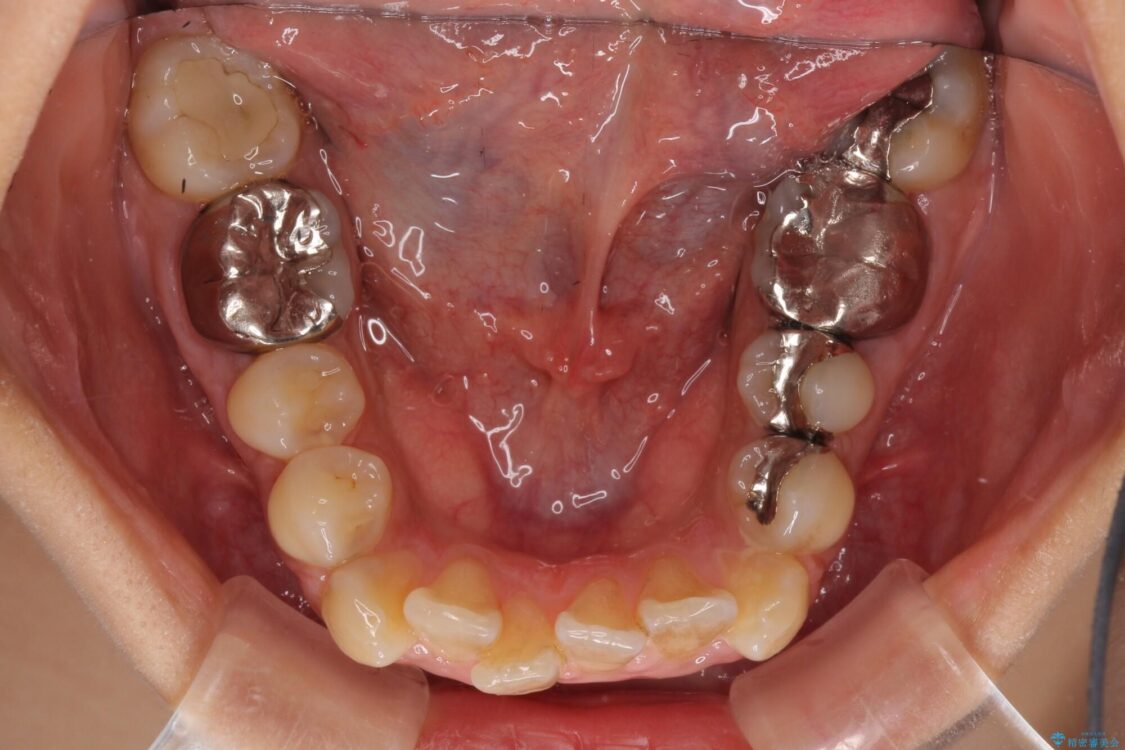

治療前

• デコボコと口元の突出感 ハーフリンガルでの抜歯矯正 治療前画像